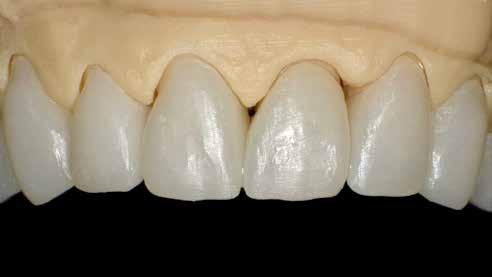

A laboratóriumban szekciós minta készült, blokk-stiftekkel (1. kép) , amelynek készítése során nagy figyelmet szenteltünk az ínymaszk (Majesthetik- Gingiimplant picodent) és a felfekvő lengőtag területének (2–6. képek)

A minta beolvasása után számítógéppel terveztük meg a híd vázát (7. kép). 0,06 mm-es cementrést terveztünk a teljes karfelület alá, 1 mmre végződve a preparáció szélétől (8–11. képek)